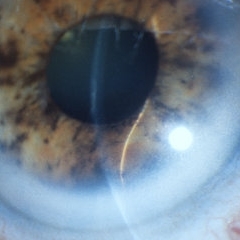

Iris Melanoma

Iris Melanoma

Jul 11 2013 by Jason S. Calhoun

Iris melanoma.

Photographer: Jason S. Calhoun, Department of Ophthalmology, Mayo Clinic Jacksonville, Florida

Condition/keywords: iris melanoma